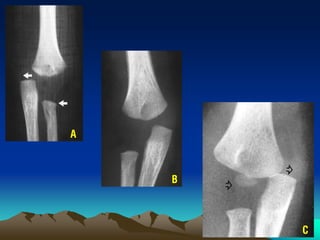

Phaân loaïi theo Gartland (1959) - Wilkins: 3 loaïi (type)

Hình A : Loaïi I: khoâng di leäch. Ñöôøng thaúng qua bôø tröôùc xöông caùnh tay ñi qua trung

taâm coát hoùa loài caàu, hình aûnh di leäch ra sau cuûa lôùp môû ñeäm

Hình B : Loaïi II: di leäch (voû sau coøn tieáp xuùc). Ñoaïn gaõy xa di leäch xoay vaø gaäp goùc

Hình C : Loaïi III : di leäch hoaøn toaøn. IIIA di leäch sau trong. IIIB di leäch sau ngoaøi

X quang:

- Gaõy ôû haønh xöông, ñöôøng gaõy naèm phía treân suïn tieáp hôïp

- Maët gaõy nham nhôû, coù hình raêng cöa (hình C)

A B C